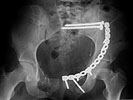

I did as suggested, I performed a 2-stage procedure (posterior sacral osteotomy and anterior take-down of left-sided rami fractures and anterior plate and percutaneous iliosacral screw fixation). It was a difficult and humbling experience. I felt as though the sacral osteotomy was complete and seemed so using intraoperative image views (inlet, outlet and true lateral of the sacrum) however after placing the distractor anteriorly I found that I could not see the sacrum well due to the bulk of the distractor itself. I then replaced it with radiolucent external fixation bars and noted widening of the left anterior SI joint.

Apparently my sacral osteotomy was not complete and the rotational correction (lateral and inferior) was occurring through the SI joint, at least anteriorly. An intraoperative x-ray showed definite improvement of the leg length discrepancy but not complete. I felt that in addition to the rotational correction the left hemipelvis also needed to move inferior as well. Due to the patient's small size, traction on her left leg simply produced pelvic obliquity and I really did not have a way of placing well leg traction which would require a post and at the same time obtain adequate intraoperative image views. Long and the short is I accepted a less than perfect reduction but with leg lengths now with less than 1 cm difference clinically and radiographically and I fused her left SI joint. No post-op nerve deficits. It was definitely a learning experience.

Any and all feed back is appreciated. Postop pics enclosed.